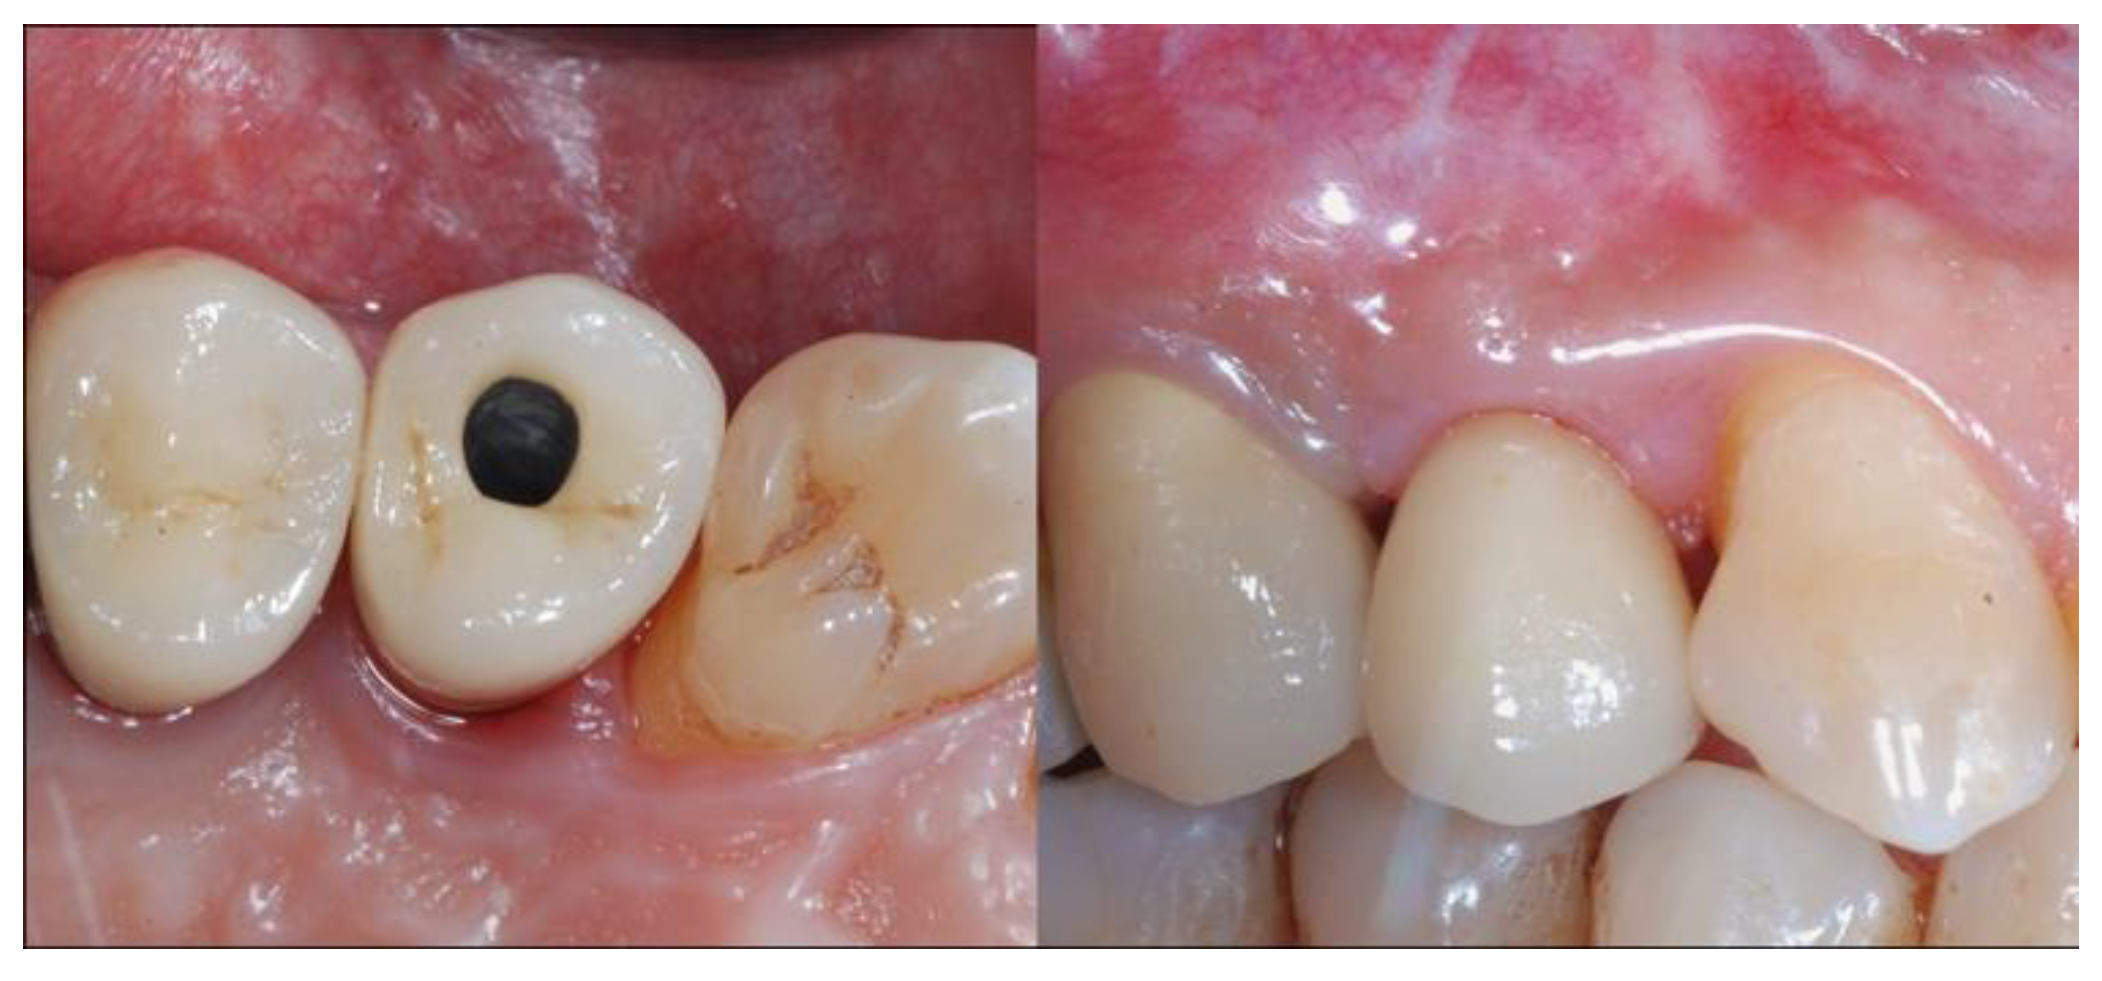

2.5. Re-Entry Surgery and Prosthetic Phases